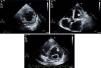

(A) Parasternal short-axis view of the mid segments. Two-layered structure of the thickened myocardium, with deep trabecular recesses in inferior, inferolateral and anterolateral segments; (B) apical 5-chamber view showing a floating thrombotic mass; (C) parasternal short-axis view showing thrombotic masses in the basal and mid segments of the anterior wall of the left ventricle.

Isolated left ventricular noncompaction (LVNC) is a form of cardiomyopathy resulting from persistence of fetal trabeculations and intertrabecular recesses within ventricular myocardium. The clinical features associated with LVNC consist of left ventricular (LV) systolic dysfunction, arrhythmias, and thromboembolic events. We report the case of a 67-year-old woman admitted to the emergency department with acute aphasia, dyspnea, and peripheral edema associated with recent-onset paroxysmal atrial fibrillation (AF) with high ventricular rate. After anticoagulation with unfractionated heparin (UFH), she was converted to stable sinus rhythm with intravenous (IV) amiodarone. She was then admitted to the intensive coronary care unit (ICCU) and treated with IV inotropes and diuretics, resulting in prompt recovery from aphasia and improvement in congestion. The echocardiogram showed a markedly dilated left ventricle with hypertrabeculation of the apex and of the inferior-inferolateral segments (noncompacted/compacted ratio 2:1), severely reduced ejection fraction (EF) (22%), and an apical thrombus. No significant carotid artery disease was found on Doppler echocardiography. She underwent implantation of an implantable cardioverter-defibrillator and was discharged in NYHA class II, under standard heart failure therapy including oral anticoagulation (OAC), with no evidence of thrombosis (Figure 1). Twelve months later, due to a major depressive episode, the patient failed to attend the scheduled heart failure clinic (HFC) follow-up and discontinued OAC. Due to recurrent dyspnea and fatigue she presented to the HFC, where an echocardiogram showed a massive LV thrombosis (Figure 2), so she was admitted to the ICCU and IV UFH was started. After two days the patient complained of chest pain; as the ECG showed marked ST segment elevation in V3-V6 she was referred to the catheterization lab. Coronary angiography revealed a thrombotic occlusion of the mid segment of the left anterior descending artery (Figure 3A); the clot was aspirated and no significant coronary artery disease (CAD) was found (Figure 3B and C). A marked increase in plasma troponin I was observed, confirming the diagnosis of acute embolic myocardial infarction (MI). Her EF fell to 15% and after two days she became hypotensive despite intra-aortic balloon pump and inotropic support, with cardiogenic shock and acute kidney failure. She was considered for a left ventricular assist device, but sepsis and multiorgan failure occurred, and death followed 25 days later.